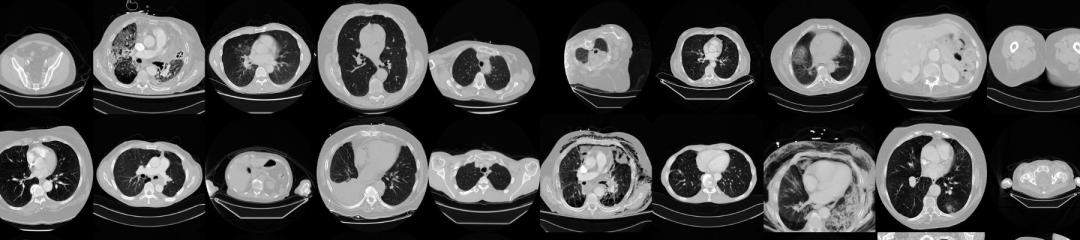

CT 医学图像

下载链接:http://suo.nz/2tQehH

该数据集旨在允许测试不同的方法来检查与使用对比度和患者年龄相关的 CT 图像数据的趋势。基本思想是识别与这些特征密切相关的图像纹理、统计模式和特征,并可能构建简单的工具,在这些图像被错误分类时自动对其进行分类(或查找可能是可疑情况、错误测量或校准不良机器的异常值)